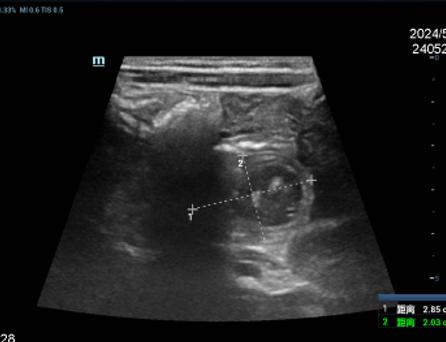

完善影像学检查,考虑存在十二指肠重复畸形可能

考虑患儿症状明显,有腹腔镜探查指征,遂安排手术,术中发现:十二指肠瓣膜致不全梗阻,予手术治疗,术后患儿恢复顺利,目前已恢复阳光快乐的生活。![]()